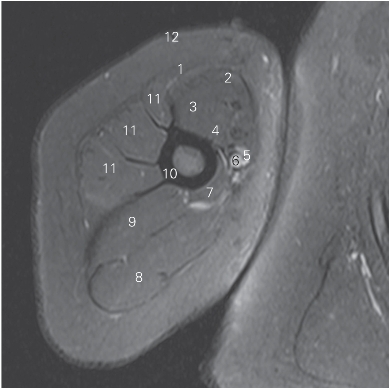

图4-26 经臂上份的横断层MR T1加权图像

1 胸大肌 ectopectoralis

2 肱二头肌短头 short head of biceps brachii

3 肱二头肌长头 long head of biceps brachii

4 喙肱肌 coracobrachialis

5 肱静脉 brachial vein

6 肱动脉 brachial artery

7 肱三头肌内侧头 medial head of triceps brachii

8 肱三头肌长头 long head of triceps brachii

9 肱三头肌外侧头 lateral head of triceps brachii

10 肱骨 humerus

11 三角肌 deltoid

12 头静脉 cephalic vein